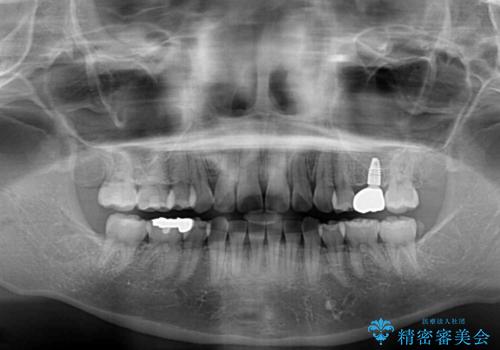

- 奥歯の欠損と、抜歯矯正の後戻りを気にして来院された患者様です。

上下前歯をワイヤー保定していましたが、強い舌の突出癖により上下ともにスペースができ、上下前歯は非接触になっていました。

また、上顎臼歯は虫歯により抜歯されてから放置されている状態でした。

舌のトレーニングをしっかりと行っていただきながらワイヤー装置により矯正治療を行い、途中でインプラントを埋入し、矯正治療後に補綴治療を行うこととしました。